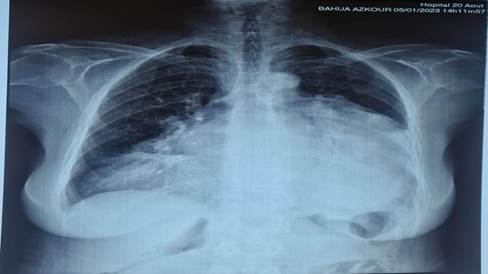

A chest X-rayrevealed a significiant rounded opacity in the lefthemithorax, which obscured the outline of both the leftmediastinal border and the ipsilateral diaphragmatic dome, consistent with the silhouette sign and indicating its antero-inferior positioning. Additionnaly a similar opacity was identified in the right lower hemithorax. (Figure 1).